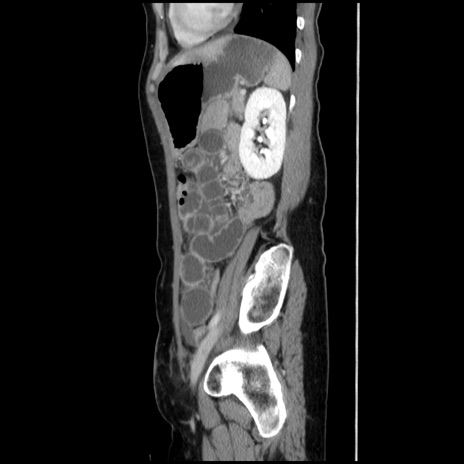

冠状断像

【症例】40歳代 女性

【主訴】上腹部痛、嘔気・嘔吐

【現病歴】約9時間前頃から急に上腹部痛、嘔気、嘔吐が出現。改善しないため救急要請。

【既往歴】子宮頚癌(広汎子宮全摘術、放射線療法)、腸閉塞

【身体所見】腹部:平坦、軟、腸雑音亢進、上腹部を中心に腹部全体に圧痛あり。

【データ】WBC 8400、CRP 0.03